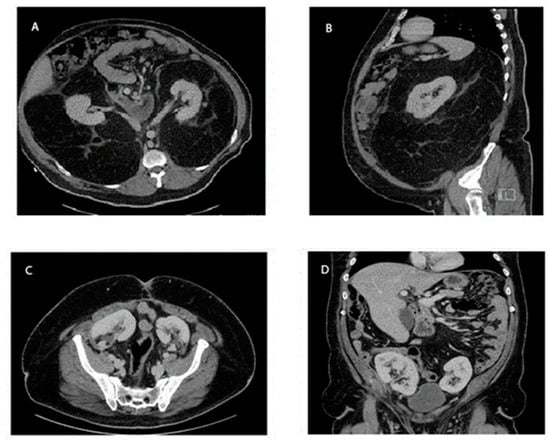

2. Detailed Case Description